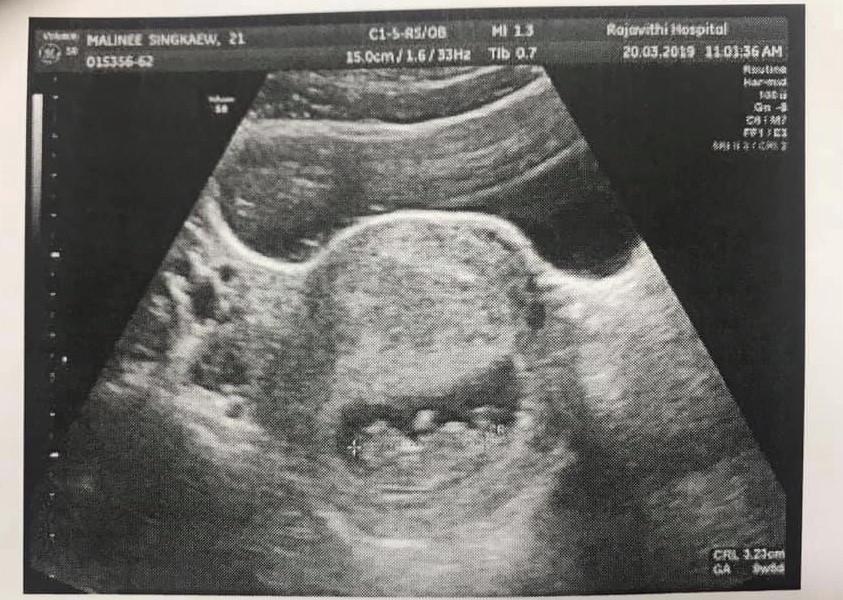

ท้องกี่เดือนถึงจะเห็นตัวน้อง

อยากทราบว่า อัตซาวกี่เดือนค่ะถึงจะเห็นน้อง #เพราะล่าสุดไปซาง์มาไม่เห็นน้อง เพราะคุนแม่ท้องได้แค่ 2สัปดาห์เองค่ะ

8 สัปดาห์ขึ้นไปจะเห็นชัดค่ะ

ของหนู7วีคก็เห็นแล้วค่ะ

เราเจอน้องตอน7วีคคะแม่

ตอน8สัปดาห์ขึ้นไปค่ะ

8สัปดาห์ค่ะ ถึงเห็น

ของเราประมาณ 8-9weekค่ะ